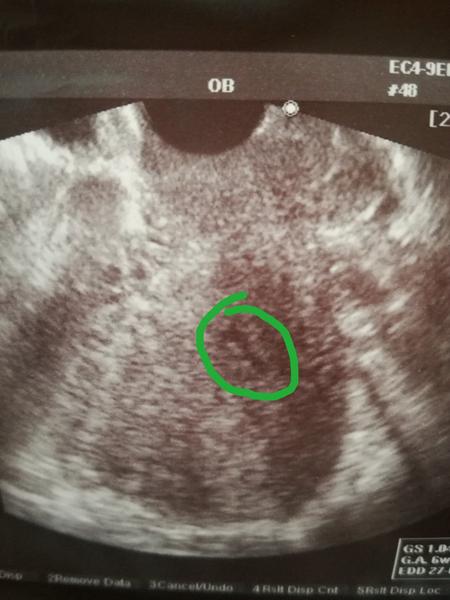

Ahoj všichni, myslela jsem, že budu trpělivá, ale kdepak..Jsem podruhé těhotná.. Ve středu 15.3. my brali krev na Hcg a potvrzeno těhotenství. 570 jednotek.Ve čtvrtek jsem byla u Dr dělala mi ultrazvuk a podle utz těhu odpovídá 6+0. Srdeční akce ještě vidět nebyla.. Chtěla jsem se zeptat, jestli hodnota hcg není malá,nebo to nemá možná vliv nevím.Pri prvním těhu mi krev nebrali, potvrzeno utz. Moc děkuji za odpovědi. Na KO jdu 30.3. ale už teď mám malinko strašáka :(

Zapomněla jsem si poznamenat poslední MS.Na Ultrazvuku mi Se řekla, že má mimi 1cm a řekla, že to je 6+0. To mám z toho, že pořád něco čtu na netu a pak mám nervy. ☹